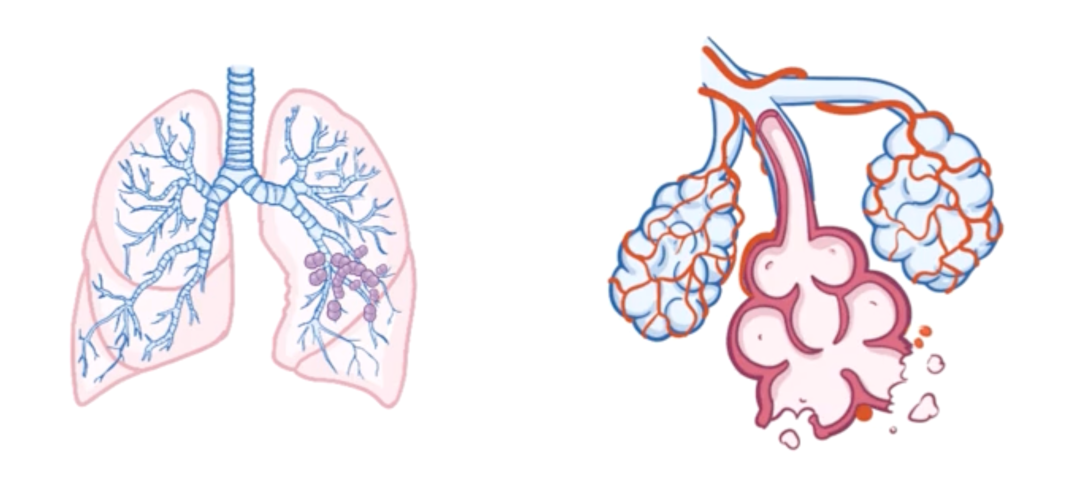

不过,肺炎链球菌最常见的致病表现还是肺炎。

它会附着在肺泡细胞——即肺细胞上,并释放肺溶素,从而破坏肺细胞和肺泡毛细血管。

肺炎会引起发热、寒战、胸痛以及咳嗽。

在严重情况下,肺炎链球菌可以穿过肺泡-毛细血管壁进入血液,引起菌血症。

随着病情进展,菌血症可能导致严重并发症,比如败血症,而败血症会造成重要器官的低灌注。